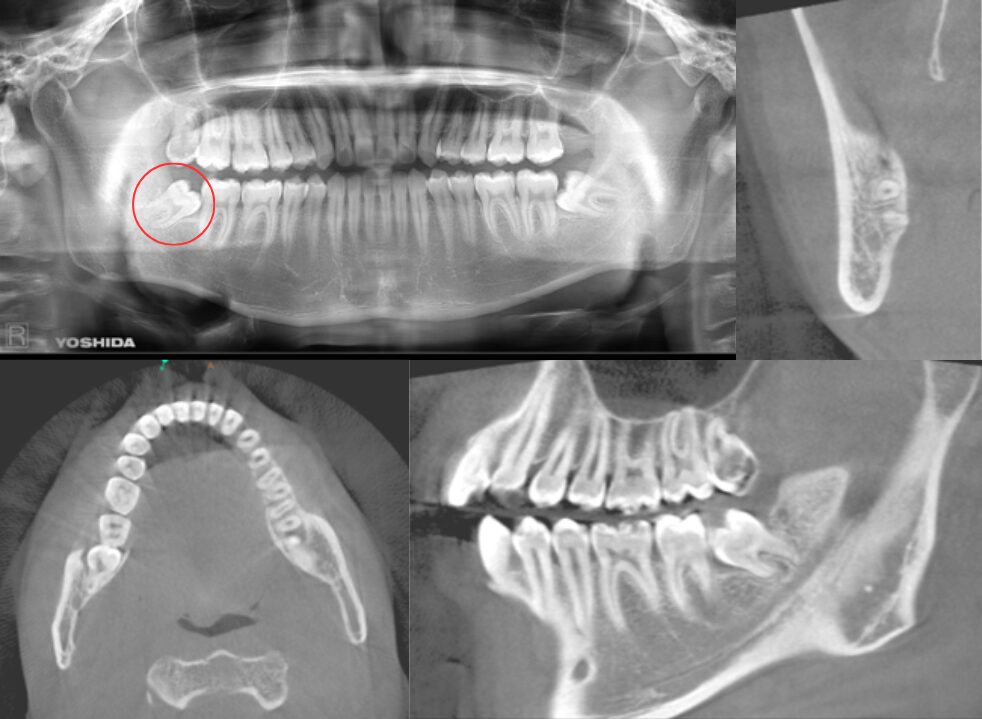

2根であり、根が彎曲している症例

| 患者情報 | 26歳 男性 |

| 手術時間 | 10分 |

| 治療内容 | 親知らず抜歯 |

| グレゴリー分類 | クラスⅡ position A |